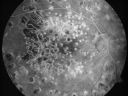

72-year-old man had macular and peripheral laser done in the past(1980's)(25 years ago). I have been seeing him for years now and I have not done any treatment. He takes Alphagan for his glaucoma. He was last here two years ago and he noticed his vision, although limited, seems about stable to him. He is diabetic for 30 years.

VISUAL ACUITY: Vision OD is 20/160, OS is 20/160. IOP: OD 15, OS 14. Posterior chamber intraocular lens is in good position in both eyes.

OD: Vertical C/D ratio is 0.5. There is extensive macular and peripheral scarring.

OS: Vertical C/D ratio is 0.5. There is extensive macular and peripheral scarring.

PHOTOGRAPHS: Photos confirm clinical findings.

FLUORESCEIN ANGIOGRAPHY: FA shows predominantly hypofluorescence corresponding to the laser spots and geographic atrophy. There is no staining or leakage in either eye nor is there any sign of any diabetic retinopathy.

Macular and Peripheral Retinal Scarring from Diabetic Laser Done 25 years previously612 views72-year-old man had macular and peripheral laser done in the past(1980's)(25 years ago). His vision, although limited, seems about stable to him. He is diabetic for 30 years. OD is 20/160, OS is 20/160.     (0 votes)